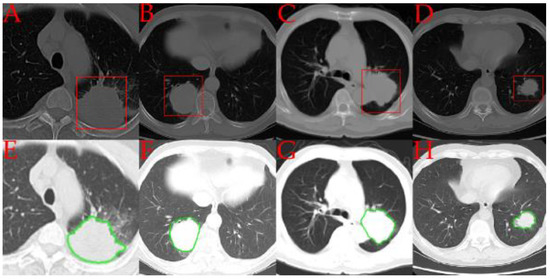

2.2. Semi-Automated Segmentation and Manual Inspection